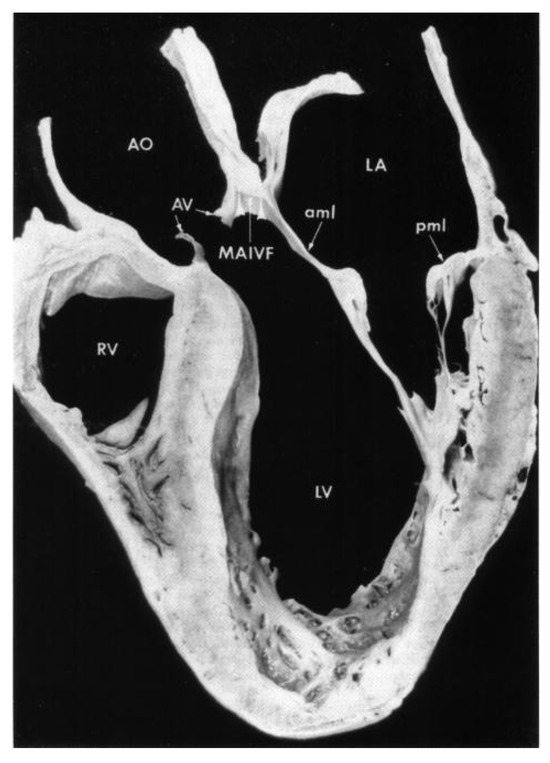

Infective Endocarditis and Complications; Surgical Indications and Management: An Integrative Review

Infective endocarditis (IE) is an infection of the endocardial surface of the heart involving native or prosthetic valves, endocardial structures, or intracardiac devices/leads. Unfortunately, incidence has risen in many settings over recent years. Historically, the incidence has been about 3–10 cases for every [...] Read more.

Infective endocarditis (IE) is an infection of the endocardial surface of the heart involving native or prosthetic valves, endocardial structures, or intracardiac devices/leads. Unfortunately, incidence has risen in many settings over recent years. Historically, the incidence has been about 3–10 cases for every 100,000 person-years and was elevated to about 13.8 cases per 100,000 person-years in 2019. Despite advancements in both detection and treatment, mortality remains high, seen with inpatient mortality rates of 18%, along with a 6-month mortality rate of 30%. IE can be a fatal condition if left untreated, in part due to the multiple serious complications that can arise. By anticipating certain complications, clinicians can be better prepared to treat patients with this condition. This article provides an integrative review of the potential complications of IE. These complications vary depending on whether the patient has native or prosthetic valves. There are cardiac, embolic, and immune-complex mediated complications that can occur. Ultimately, IE can lead to multiorgan dysfunction and result in septic shock and disseminated intravascular coagulopathy (DIC). While the mainstay of treatment for IE remains medical, certain cases require surgical intervention. Due to their close relationship, a review of the indications for surgery in the treatment of IE is also presented in this article. By having a general scope of the complications of IE and when to get a surgical consult, clinicians can be better equipped to care for patients with a potentially fatal condition that is becoming increasingly more frequent. Full article